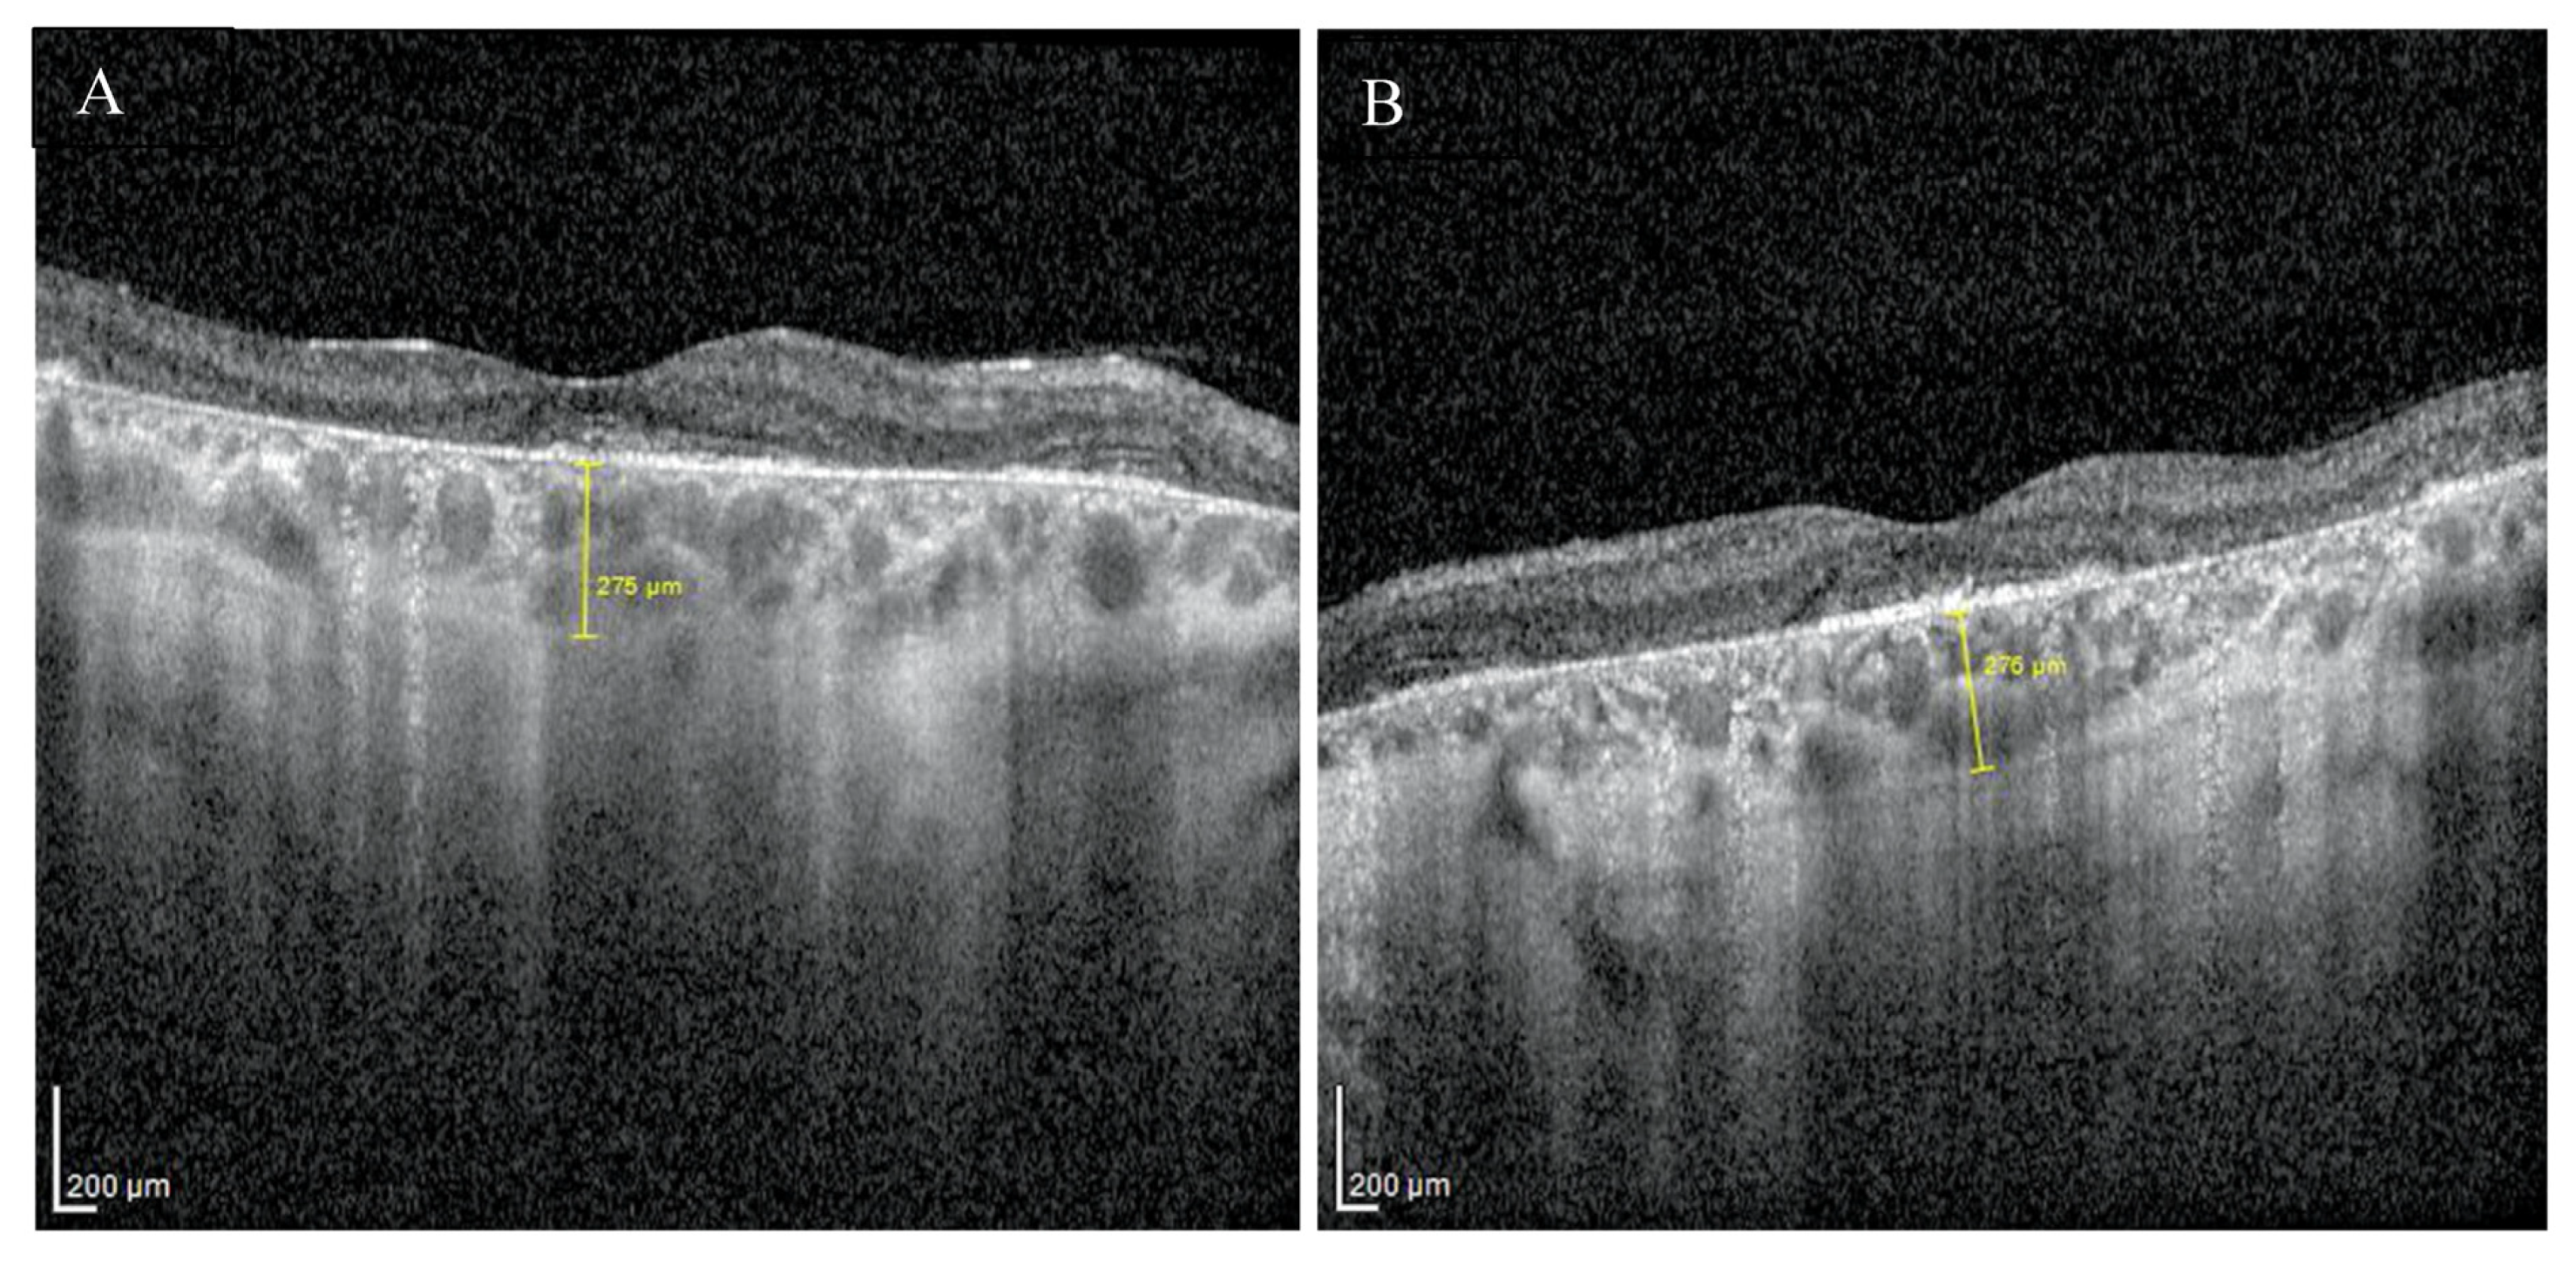

Enhanced depth imaging optical coherence tomography (EDI-OCT) pictures revealed foveal thinning with distortion and loss of the outer nuclear layer (ONL), external limiting membrane (ELM), ellipsoid zone (EZ), and retinal pigment epithelium (RPE) bilaterally. The central foveal thickness was 175 μm for the RE and 170 μm for the LE, whereas the choroid thickness (CT) was 275 μm and 276 μm, respectively (Figure 2A,B). Static perimetry demonstrated a deepening central scotoma with saving peripheral vision in OU (Figure 3A,B).

Figure 2.

EDI-OCT pictures of the right (A) and the left (B) macula revealed atrophy of outer layers with normal choroid thickness.